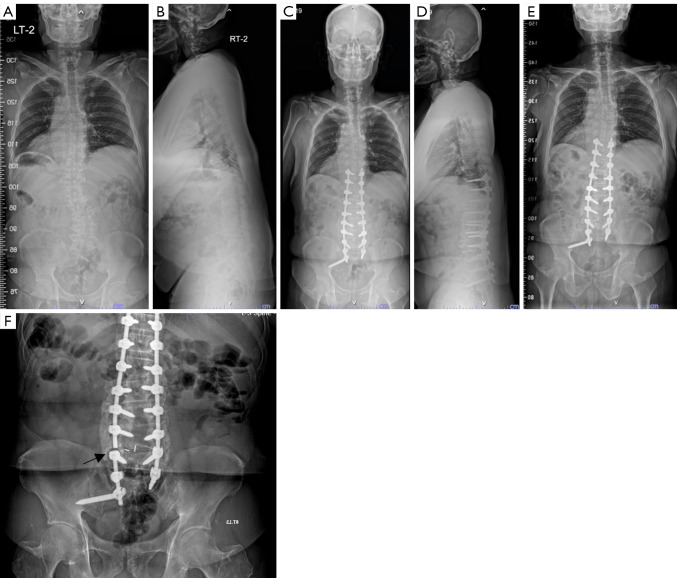

Abstract Image